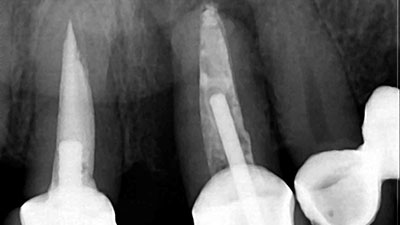

The following case presentation will illustrate an anterior maxillary reconstruction with the use of dental implants and fixed prosthodontics. Our patient (P.C.) presented to the office with the pre-existing dental treatment done over 10 years ago as illustrated in Figures 1 and 2. Due to a large diastema between 11 and 21, the previous practitioner … Read more